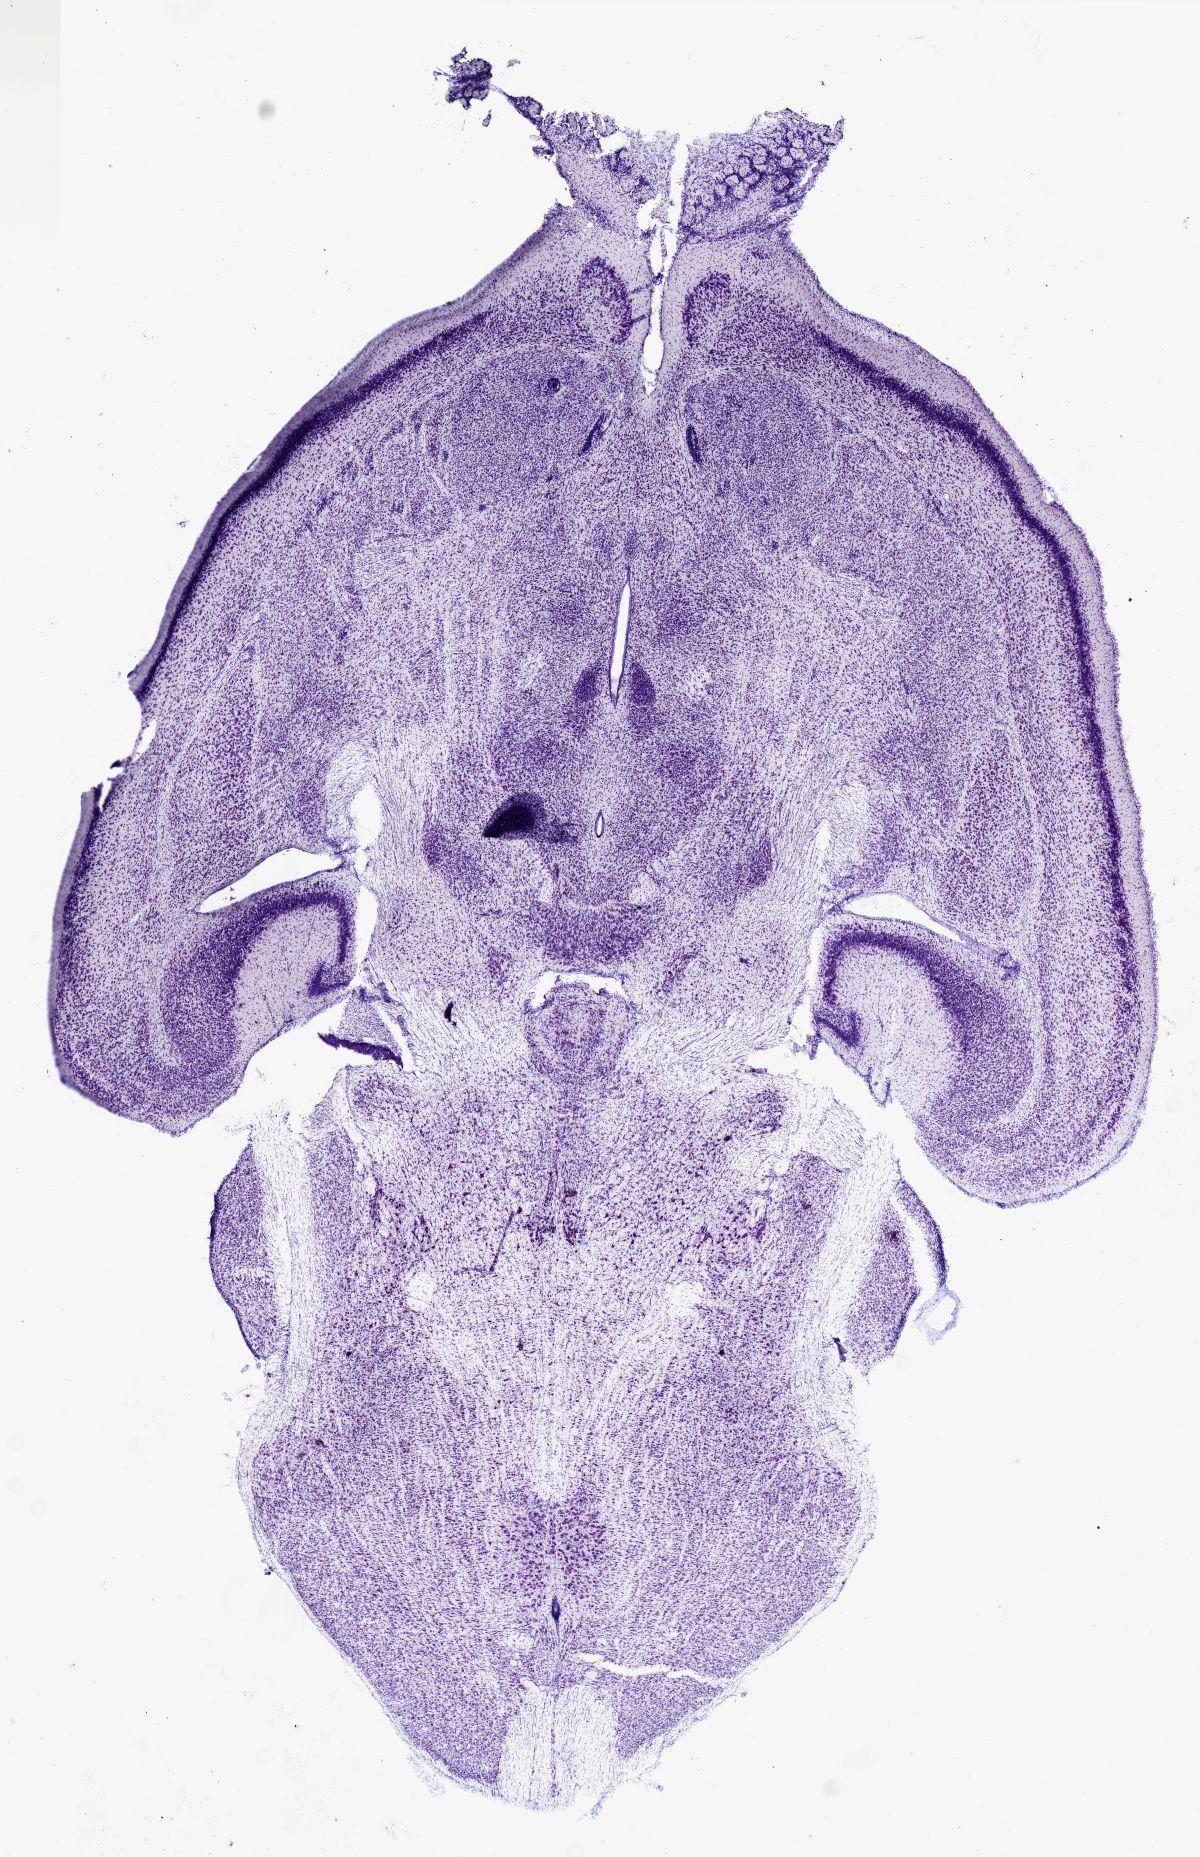

Datasets -> Mus Musculus -> Nissl, horizontal, histo, Whole-Brain, adult

[ Metadata ]   ·   Source: Shawn Mikula

Displaying Sections 41 thru 67 of 67 Sections for this Dataset